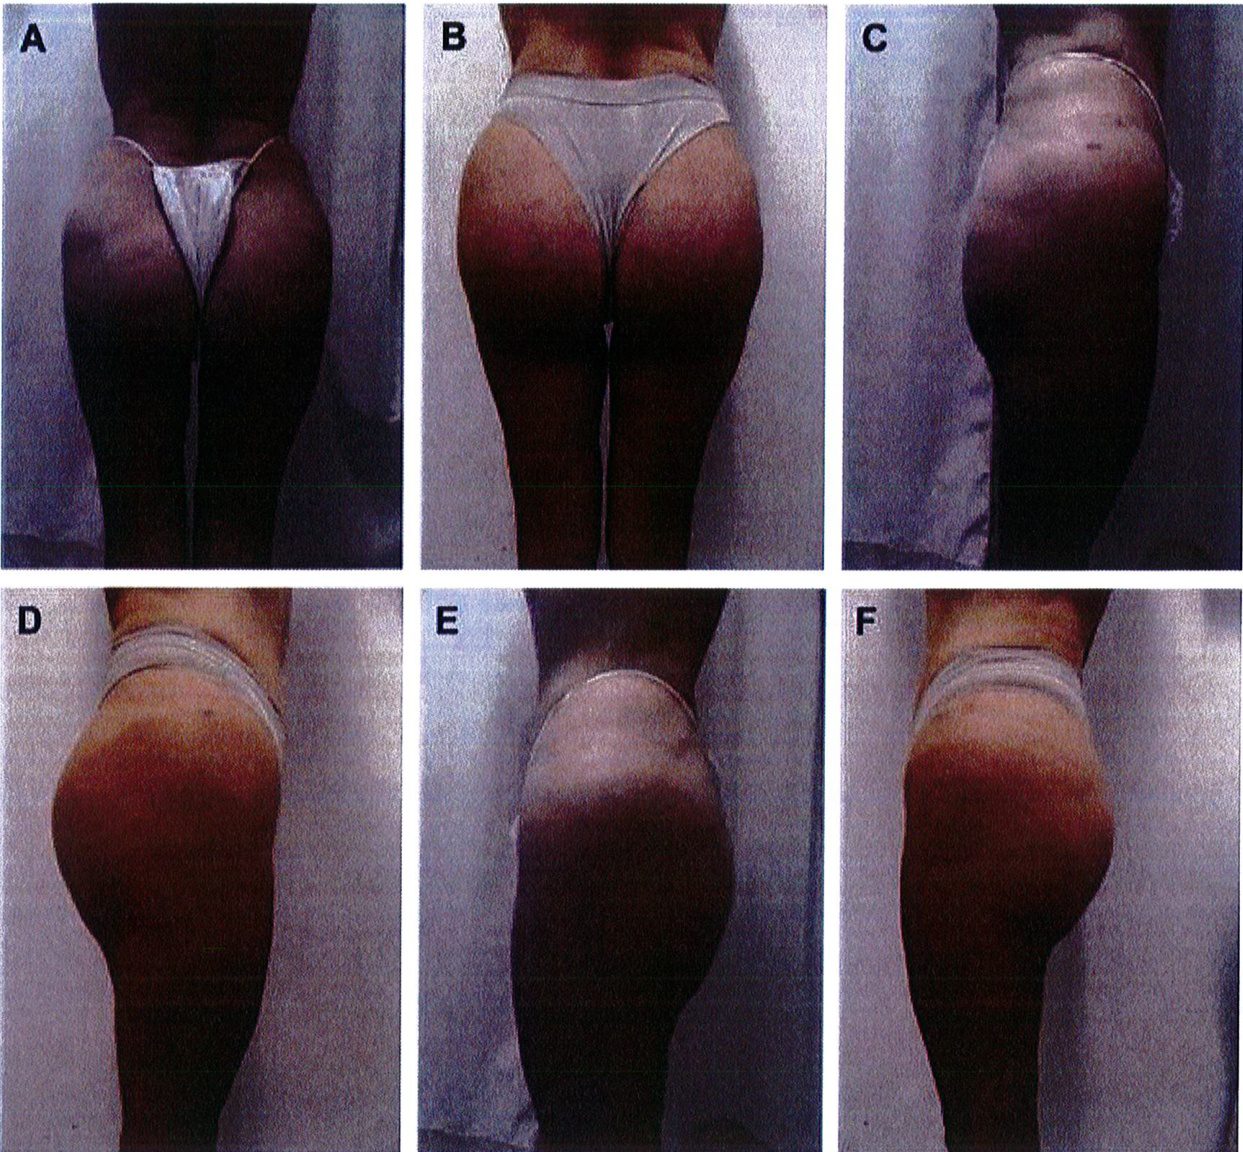

Kết quả phẫu thuật quan sát trên Hình. 3-5.

Hình. 3. (A-H) Tiền phẫu, chu phẫu và sau hậu phẫu 6 tháng của một bệnh nhân nữ 38 tuổi đươc ghép túi đôn mông với thể tích 330 cm3.

Hình. 4. (A-I) Hình ảnh tiền phẫu, chu phẫu và sau hậu phẫu 11 tháng của một phụ nữ 25 tuổi đã được thực hiện hút mỡ vùng éo, hông và sau xương vùng, đồng thời ghép khối cấy thể tích 270cm3.

Hình. 5. (A-F) Hình ảnh tiền phẫu và sau hậu phầu 4 tháng của bệnh nhân 67 tuổi, ghép khối implant thể tích 300 cm3.